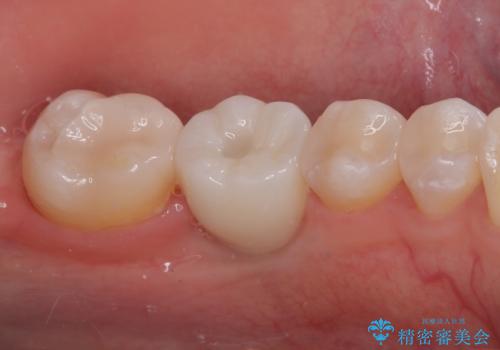

- ブリッジの歯のないところにインプラントを入れて、銀歯を白くやり替えたいと来院された患者様です。

歯の欠損している箇所にはインプラント治療をし、銀歯と仮詰めの部分はセラミックインレーにて補綴することとしました。

すべての治療の前に親知らずの抜歯も行っています。